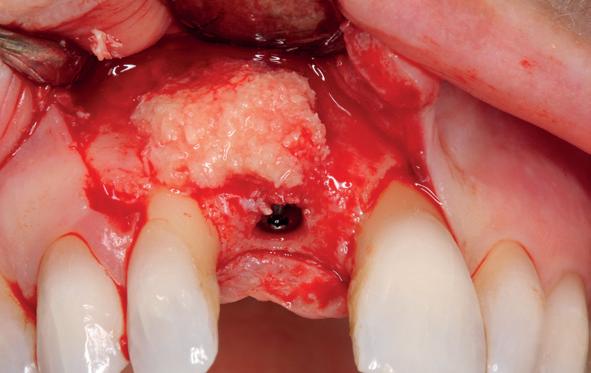

Ongeveer drie maanden na de totaal extractie zien wij de patiënt terug voor verder klinisch en röntgenologisch onderzoek en het opstellen van het definitieve implantologische behandelplan. Gebitsmodellen worden gemaakt waarbij de kaakwallen worden gescand ter voorbereiding van de chirurgie. Van groot belang is het vervaardigen van een CBCT-scan om zowel de breedte als de hoogte van de processus te bepalen in de boven- en onderkaak. Daarnaast is het van belang de sinusbodem goed in kaart te brengen en eventuele septa in beeld te brengen. Ook in de onderkaak is het noodzakelijk te achterhalen hoe de canalis mandibularis loopt en waar precies het foramen mentale zich bevindt. Bij patiënt G. wordt al snel duidelijk dat de kaakbreedte in zowel de onder- als de bovenkaak vrij smal verloopt. Een botopbouw kan daarom niet voorkomen worden en bij de voorbereiding van het plaatsen van de implantaten zal daarom ook de botopbouw per kaak opgenomen moeten worden in het behandelplan. Een laterale botopbouw met een sinuslift in het eerste kwadrant is vrijwel onvermijdelijk.

Voor de uitvoering van de implantologische chirurgie is preoperatief een boorsjabloon vervaardigd, zodat op de juiste positie de implantaten geplaatst kunnen worden. Zonder een boorsjabloon is de juiste positionering vrijwel onmogelijk. De voorbereiding van de chirurgie zelf lijkt in de uitvoering van het behandelplan het meest voorspelbaar. Buiten de mond kan uitgebreid de tijd genomen worden voor de voorbereiding. Ook de bespreking van de posities van de implantaten kan interdisciplinair worden besproken met de restauratieve tandarts (dr. Paul de Kok) en de tandtechnicus (Michel Castro) van 4Dental Am-

5. Implantaten geplaatst op geleide van een boorsjabloon; botopbouw met sinuslift volgens de GBR-techniek en Caldwell Luc methode; materialen: Oragraft & BioOss, Ossix membr, hyaluronzuur. In de BK is gekozen voor Bego implantaten (Bego SC en RSX 3,75x 11,5 & 13mm).

6. In het front zijn Bego 3,25mm

sterdam. Een interdisciplinaire benadering van deze behandeling is dus cruciaal.

Tijdens de chirurgische behandeling worden na het afschuiven van de flap de posities bepaald van de implantaten met de boorsjabloon. In de bovenkaak worden 7 implantaten geplaatst en in de onderkaak 8

implantaten geplaatst terwijl in de zijdelingse delen voor een bredere diameter (3,75 & 4,1) is gekozen, met lengte 8,5 en 10mm.

(zie foto’s chirurgie en OPT’s). Gekozen is voor Bego SC & RSX Pro van een relatief smalle diameter (3,253,75). Alleen in de molaarstreek valt de keuze op een 4,1 mm in diameter. De lengte varieert tussen 8,5 en 13 mm afhankelijk van de ligging van de nervus alveolaris inferior en het foramen mentale als de neusbodem en de sinusholte. De keuze van de diameter wordt mede bepaald door de breedte van de processus ondanks de uit te voeren laterale botopbouw. Indien mogelijk gaat de voorkeur uit naar het plaatsen van implantaten in autoloog en daarmee vitaal bot.

Lateraal van de implantaten wordt de kaak fors uitgebouwd volgens de Hybride GBR-techniek met Oragraft (allograft) van Lifenet die wordt vermengd tot een cocktail met BioOss (xenograft) van Geistlich, autoloog geoogste botsnippers en verzameld bloed uit het wondgebied. De botgraft wordt bedekt met een Ossix (crossed linked) membraan en met Hyadent (hyaluronzuur) overspoten. De sinuslift wordt gelijktijdig met de laterale botopbouw volgens de Caldwell Luc methode uitgevoerd en de uitgeprepareerde holte opgevuld met de botgraft. De flaps worden eerst horizontaal ontlast (gemobiliseerd) en vervolgens naar elkaar toe gehecht met vicryl rapide. Daarbij wordt gebruikgemaakt van horizontale matrassen, zodat de wondranden passief tegen elkaar